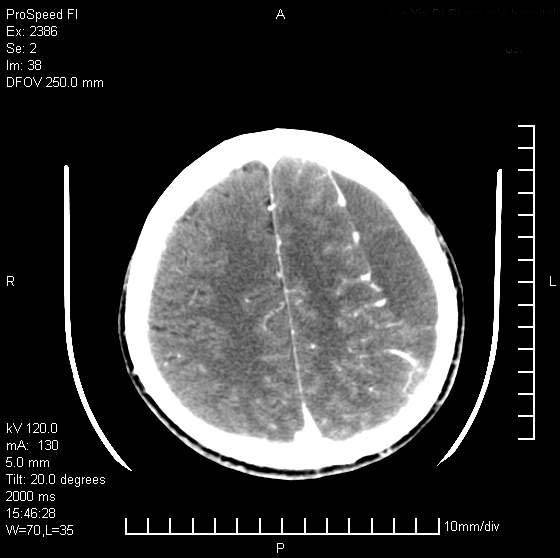

以下是引用天南地北在2007-9-19 18:43:00的发言:[br]典型慢性硬膜外血肿[br][br][本贴已被 天南地北 于 2007-9-19 18:44:11 修改过]

以下是引用曼一拍在2007-9-20 11:06:00的发言:[br]支持慢性硬膜下血肿.[br]慢性硬膜下积液:血肿有包膜,ct值稍高于脑脊液,增强可有染色。不典型者血肿可多呈梭形.是硬脑膜与蛛网膜之间的潜在腔隙内的血肿。[br]鉴别:[br]1\\硬膜外血肿:是颅脑外伤后脑膜或板障内血管破裂,血液在颅骨与硬膜之间积聚所致.通常是脑膜动脉破裂,也可因静脉窦破裂或颅骨的板障静脉出血,发生于外伤的着力部,常与颅骨骨折并存。脑膜动脉出血则急,若是板障静脉出血在则可有慢性。[br]2\\硬膜下积液:(硬膜下水瘤)[br]是由于蛛网膜破裂,脑脊液经蛛网膜破口进入硬膜下腔不能回流。或水肿阻塞而形成。[br]ct表现:颅骨内板下方新月形低密度区近似脑脊液密度;占位效应清,周围无脑水肿。[br]